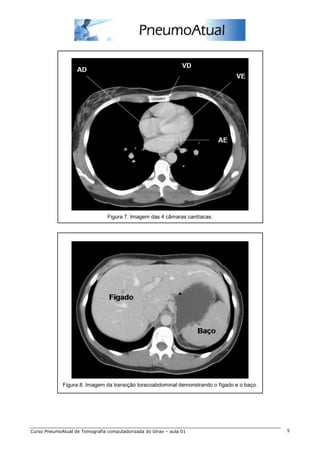

Figura 7. Imagem das 4 câmaras cardíacas.

Figura 8. Imagem da transição toracoabdominal demonstrando o fígado e o baço.